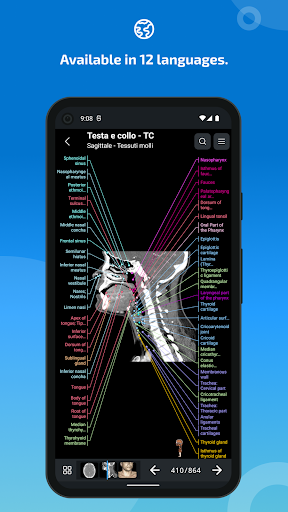

e-Anatomy memiliki lebih dari 26.000 gambar yang berisi serangkaian gambar dalam tampilan aksial, koronal, dan sagital serta radiografi, angiografi, gambar diseksi, bagan anatomi, dan ilustrasi. Semua gambar medis diberi label dengan cermat, lebih dari 967.000 label tersedia dalam 12 bahasa termasuk Terminologia Anatomica Latin.

- Ganti bahasa dengan satu sentuhan tombol